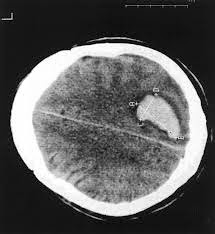

PHILADELPHIA — A new study finds a link between vitamin C depletion and increased risk for intracerebral hemorrhage (ICH).

In a case–control study, researchers found vitamin C depletion was more common among ICH cases than matched controls.